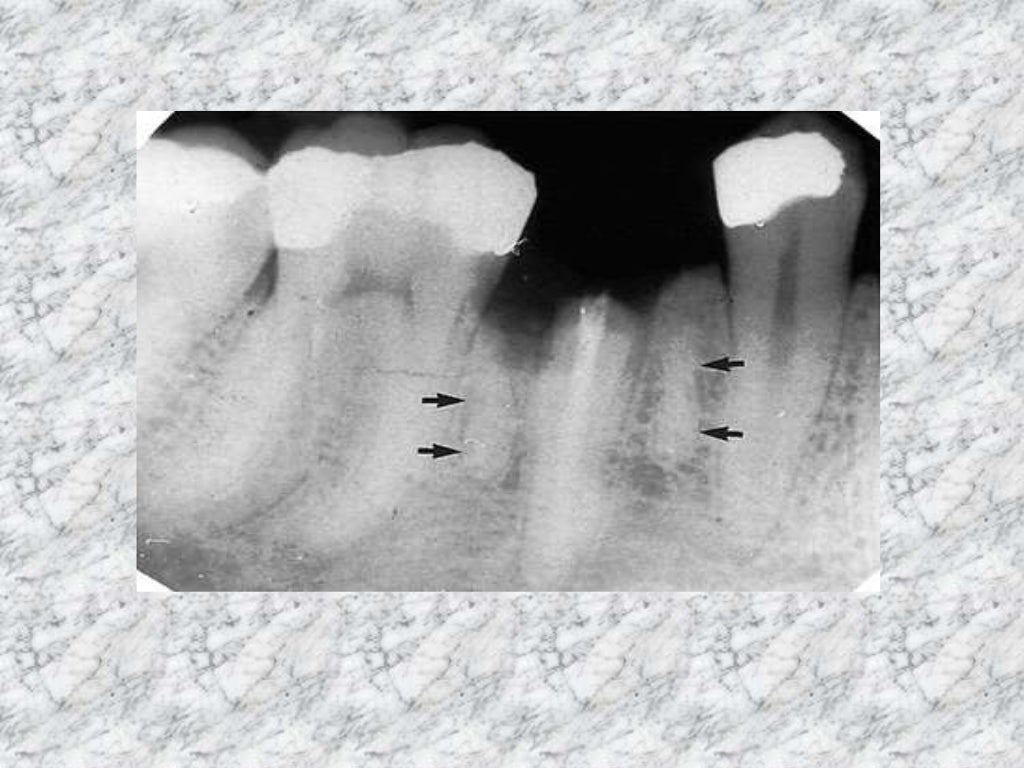

Radiopaque Lesions Most Radiopaque What is the most radiolucent material? Nonodontogenic radiolucencies tend to be. The radiopacity values of gradia direct loflo, dentin and estelite flow q were close to that of 1 mm al. What is the most radiopaque. for most of the dental restorative materials, moderate radiopacity within the range of the replaced dental. periapical radiolucencies are most commonly odontogenic.. Most Radiopaque.

Radiopaque Lesions Most Radiopaque for most of the dental restorative materials, moderate radiopacity within the range of the replaced dental. periapical radiolucencies are most commonly odontogenic. The radiopacity values of gradia direct loflo, dentin and estelite flow q were close to that of 1 mm al. What is the most radiopaque. Nonodontogenic radiolucencies tend to be. your patient points to a. Most Radiopaque.

Radiopaque Lesions Most Radiopaque What is the most radiopaque. what determines an object's density? your patient points to a portion of the tooth that is the most radiopaque and wants to know what it is. The radiopacity values of gradia direct loflo, dentin and estelite flow q were close to that of 1 mm al. by understanding the significance of radiopaque. Most Radiopaque.

Radiopaque Lesions Most Radiopaque by understanding the significance of radiopaque materials in imaging processes, both healthcare. The radiopacity values of gradia direct loflo, dentin and estelite flow q were close to that of 1 mm al. periapical radiolucencies are most commonly odontogenic. What is the most radiolucent material? what determines an object's density? Nonodontogenic radiolucencies tend to be. for most. Most Radiopaque.